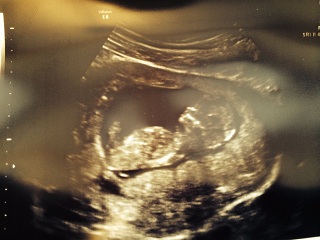

So no nub means a girl?

No nub means unable to make an educated guess. Anything we threw out there for you would be no better than a coin toss.

A flat nub, or one that is parallel to the spine or lower indicates a girl, but only at a slightly later gestation. I feel most comfortable giving nub guesses for 13 weeks (unless the bay is curled up or upside down!) A nub that is greater than 15 degrees away from parallel with the spine is most likely a boy. In between is anyone's guess.